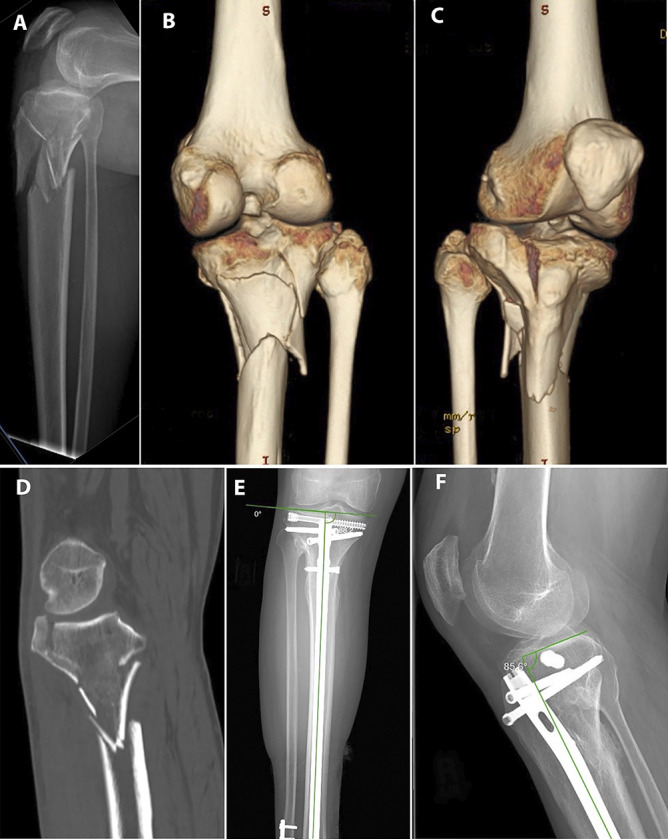

目的:比较髌上髓内钉(IMN)与双钢板切开复位内固定(ORIF)治疗双髁胫骨平台骨折(OTA/ ao41 - c2 /C3)的关节复位和对准维持效果。设计:回顾性队列研究。环境:单一一级学术创伤中心。患者/参与者:2012年7月至2022年7月期间接受治疗的58名成年人(28名IMN, 30名ORIF);各组根据年龄、体重指数和骨折类型进行匹配。干预措施:与标准开放入路行双钢板ORIF相比,采用≥1枚独立拉力螺钉的半扩展髌上IMN。主要结果测量:关节线凹陷、髁突加宽、胫骨内侧近端角(MPTA)和胫骨后部近端角(PPTA)愈合(12个月)。结果:ORIF队列的初始位移更大(关节线8.2 mm vs 5.6 mm, P = 0.014;扩大7.2 mm vs 5.8 mm, P = 0.150)。在12个月时,愈合的宽度(0.6 mm IMN vs 1.0 mm ORIF, P = 0.856),愈合的凹陷(2.0 mm vs 1.1 mm, P = 0.991), MPTA(89.9°vs 89.6°,P = 0.699)和PPTA(11.3°vs 9.8°,P = 0.078)没有差异。没有发生需要修正的二次复位损失。结论:髌上IMN维持了OTA/AO C1、C2和某些C3骨折愈合后的关节线移位、髁突加宽、MPTA和PPTA。手术恢复和维持MPTA和PPTA。该技术在胫骨平台骨折的ORIF使软组织包膜处于危险中或在其他情况下首选髓内植入物的情况下可能有用。证据等级:三级。

Objectives: Compare maintenance of articular reduction and alignment in bicondylar tibial plateau fractures (OTA/AO 41-C2/C3) treated with suprapatellar intramedullary nailing (IMN) versus dual-plate open reduction and internal fixation (ORIF).

Intervention: Semiextended suprapatellar IMN with ≥1 independent lag screw compared with dual-plate ORIF performed through standard open approaches.

Main outcome measurements: Joint-line depression, condylar widening, medial proximal tibial angle (MPTA), and posterior proximal tibial angle (PPTA) at union (12 months).

Results: Initial displacement was greater in the ORIF cohort (joint-line 8.2 mm vs. 5.6 mm, P = 0.014; widening 7.2 mm vs. 5.8 mm, P = 0.150). At 12 months, healed widening (0.6 mm IMN vs. 1.0 mm ORIF, P = 0.856), healed depression (2.0 mm vs. 1.1 mm, P = 0.991), MPTA (89.9° vs. 89.6°, P = 0.699), and PPTA (11.3° vs. 9.8°, P = 0.078) did not differ. No secondary loss of reduction requiring revision occurred.

Conclusion: Suprapatellar IMN maintained healed joint line displacement, condylar widening, MPTA, and PPTA in OTA/AO C1, C2, and certain C3 fractures. The MPTA and PPTA were surgically restored and maintained. This technique may be useful in certain circumstances where ORIF of the tibial plateau fractures places the soft tissue envelope at risk or where an intramedullary implant is otherwise preferred.